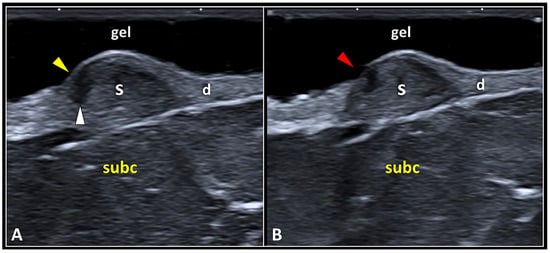

Normally, the hyperechoic epidermis covers the underlying hypoechoic scar tissue located in the dermis. In some patients, the progressive remodeling of the scar may lead to its detachment from the overlying epidermis—i.e., dermo-epidermal dissociation. This condition can progressively evolve into a focal disruption of the epidermis with exposure of the underlying scar tissue (Figure 4). Sonographically, a focal discontinuity of the hyperechoic line representing the epidermis can be observed coupled with a hypo/anechoic focus within the underlying dermal tissue.

Figure 4.

The dermo-epidermal dissociation. Retraction of the scar tissue (S) may generate a gap (white arrowhead) in between the epidermal (yellow arrowhead) and dermal (d) layers, i.e., dermo-epidermal dissociation (A). This condition can evolve in a focal discontinuity of the epidermis (red arrowhead), probably due to a local hypo-vascularization, with superficial exposure of the underlying scarring tissue (B). subc: subcutaneous tissue.

Focal injury of the epidermal layer overlying the site of dermo-epidermal dissociation is most likely related to local hypoperfusion—with mechanical disruption of the hemidesmosomal adhesion proteins at their attachment to the underlying laminae (lucida and densa). Yet, as previously mentioned, there are terminal arterioles, capillaries, and postcapillary venules arranged in a “candelabra-like loop system” located into each dermal papilla, with ascending arterial and descending venous branches [26,31]. The authors strongly suggest accurately reporting the aforementioned sonographic patterns of the epidermis in patients with skin scars—to plan a suitable treatment to avoid infection of the superficial soft tissues. For instance, special bandages to protect the scarring tissue, and/or topical pharmacological agents to create a protective film over the focal discontinuity of the epidermis can be used. Likewise, in patients with a clinical suspicion of epidermal interruption (after the physical examination), a sterile gel should be adopted to prepare the soft standing pad over the skin scar before the US assessment.